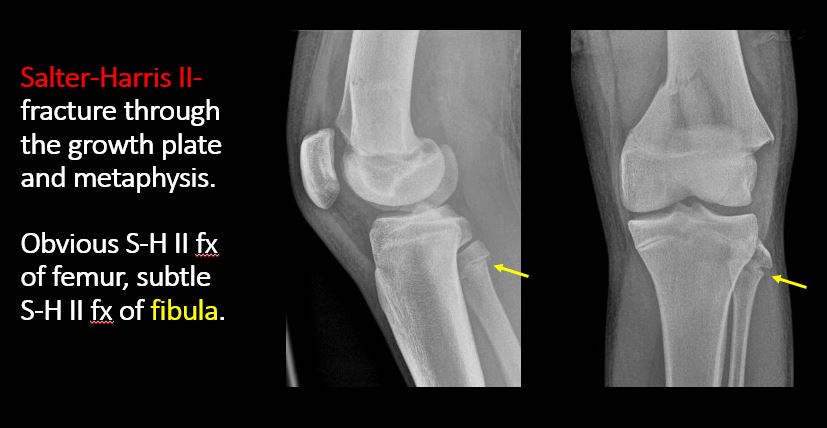

There is a fracture through the physis which then extends into the metaphysis with or without angulation or displacement (S-H II). [Yes/No]

The apophysis, epicondyle, secondary ossification center, or accessory ossicle is displaced or otherwise abnormal (e.g. avulsed ASIS, medial epicondyle of the humerus, etc). [Yes/No]